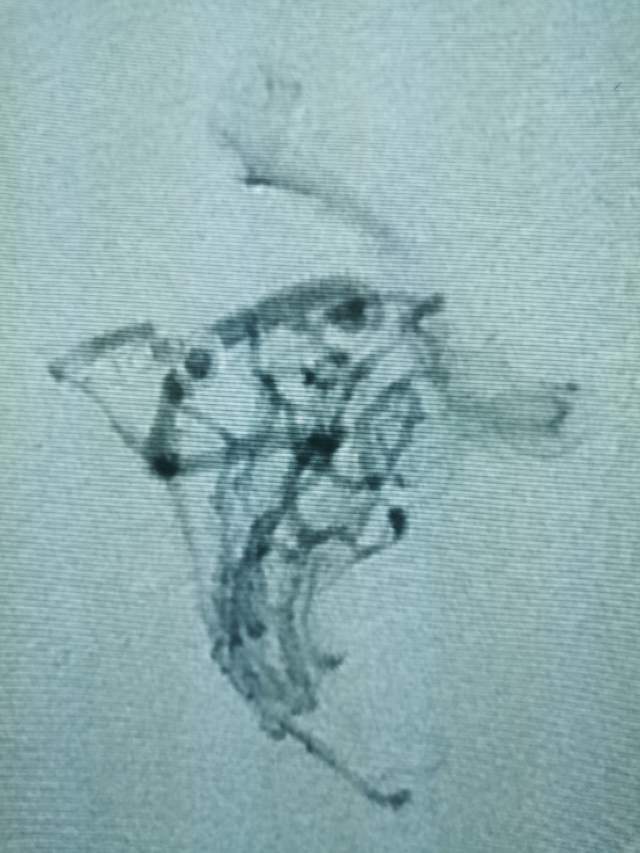

第二次手术:继续采用削减周围边支的方法,术中显示3个瘤样凸起,如果提前闭塞引流静脉,这些薄弱结构会引起颅内出血哦,层层拨开畸形上面的面纱,最后安全的解决了畸形